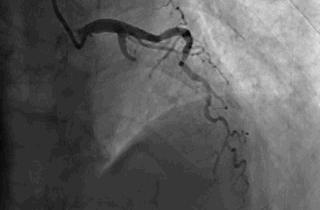

▲闭塞的前降支血管开通了,心肌的血供恢复了

【逃生秘笈】

出门在外发生心梗,如果身边没有亲人,能够救你一命的只有医生!请相信他,果断签字手术。

不要等待配偶,不要等孩子,更不要犯傻地要求回当地手术。命运,此刻就掌握在你自己手中。